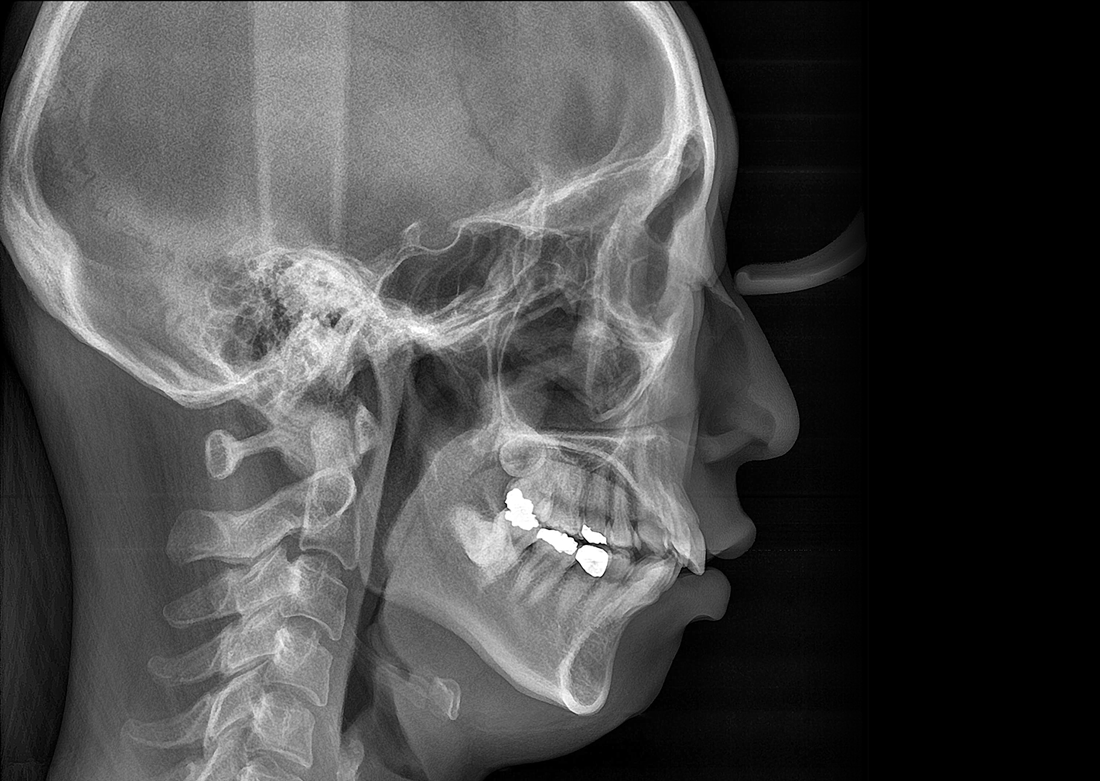

A panoráma-, CT- és cefalometriai* szkennelési módok segítségével pontos diagnózis állítható fel.

ULTRAGYORS KEFALOMETRIA*

A gyors szkennelési idő csökkenti a páciens mozgásából eredő képtorzulást, és alacsony dózis mellett minimalizálja a sugárterhelést.

KLİNIKAI KÉPEK

Kiváló diagnosztikai képalkotás több éves tapasztalattal és szakértelemmel.